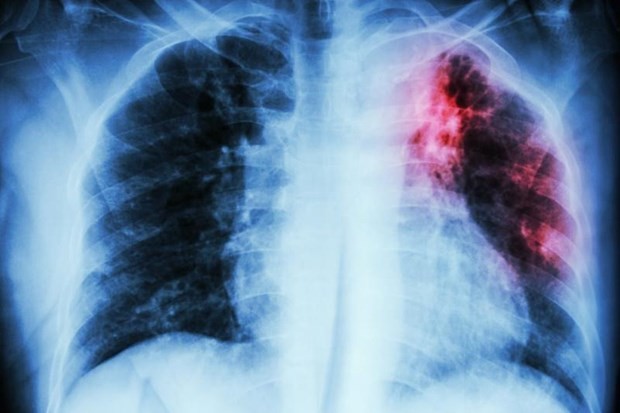

| Ung thư phổi là căn bệnh nguy hiểm mà nhiều người mắc phải. (Nguồn: Inform.kz) |